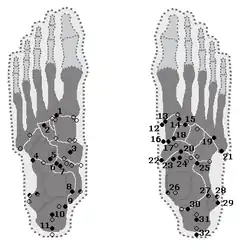

Insbesondere an den Fußwurzelknochen können eine Reihe von akzessorischen Fußwurzelknochen beobachtet werden. Sie sind teilweise weitverbreitet und in vielen Fällen symptomlos. Meist handelt es sich um Zufallsbefunde bei einer Röntgenuntersuchung. Das Os tibiale externum ist beispielsweise bei etwa einem Fünftel aller Erwachsenen vorhanden.[11] Das Os trigonum kommt bei 3–15 % der Erwachsenen vor.